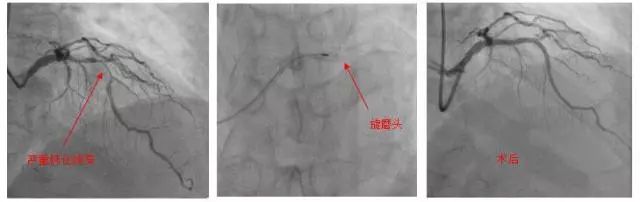

冠状动脉旋磨术处理严重钙化病变

近日,张大爷慕名来到北京大学国际医院血汗管内科就诊时,杨告捷主任医师表示冠状动脉钙化斑块有些像石头一样坚硬,传统的球囊扩张常常难以奏效,强行扩张还可能导致血管撕裂或穿孔,只有尝试旋磨术来解决这一难题。

冠脉旋磨术,是使用一个头端布满微钻石的磨头,高速旋转下反复打磨钙化病变,以期达到钙化变薄、易于扩张的目的。因为技术要求高,国内仅少数中心可开展。

在与张大爷进行详细说明后,杨告捷主任医师和陈学智副主任医师为张大爷进行了手术,在反复的旋磨、扩张后,成功地在前降支病变处植入了两枚支架,开通了冠脉血流。